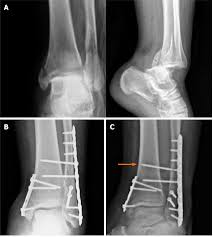

My guess (purely based off 1 clip of watching the injury lol) is they’re putting in screws for a syndesmosis and a plate for the tib/fib like the pic at the bottom but we shall wait and see!